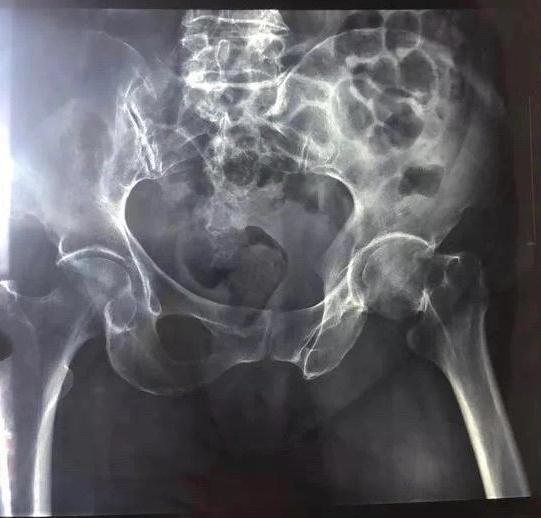

据汤女士的诊断报告单显示,汤女士的左侧股骨颈骨骨折,骨皮质不连续,断端成角,周围软组织肿胀。

7月31日上午,汤女士在医院安装了骨折部位的支架。据王女士介绍,目前,汤女士较为虚弱,情绪已经平稳下来。